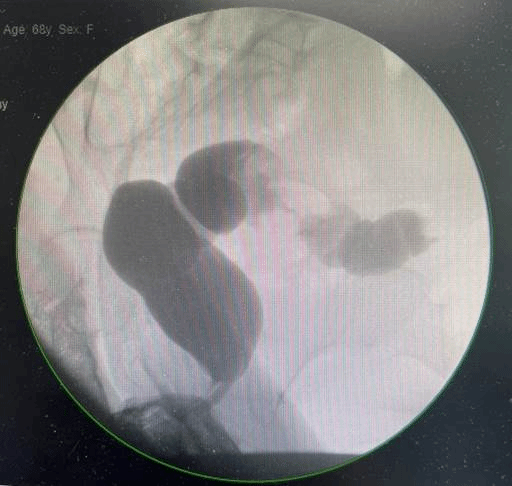

直肠占位伴狭窄

68岁的黄女士因感染新冠病毒导致肺炎来到哈医大一院治疗。入院后,完善相关检查发现左肾和直肠两处脏器分别有原发占位性病变,需要尽快手术治疗。

左肾占位

泌尿外科三病房副主任刘赞教授介绍,两处脏器原发占位性病变,从安全的角度看要准备二期手术,即先切除肾脏肿瘤后,待患者身体恢复再行直肠肿瘤切除术。但分两次根治患者的肿瘤,对患者的身体和家庭都会造成很大负担,而且不及时切除直肠上的肿瘤,如果出现快速增大或转移到其他部位,对患者的生命健康就会造成更严重的威胁。且在疫情期间,多次往返医院治疗,也会增高再次感染新冠病毒的几率。